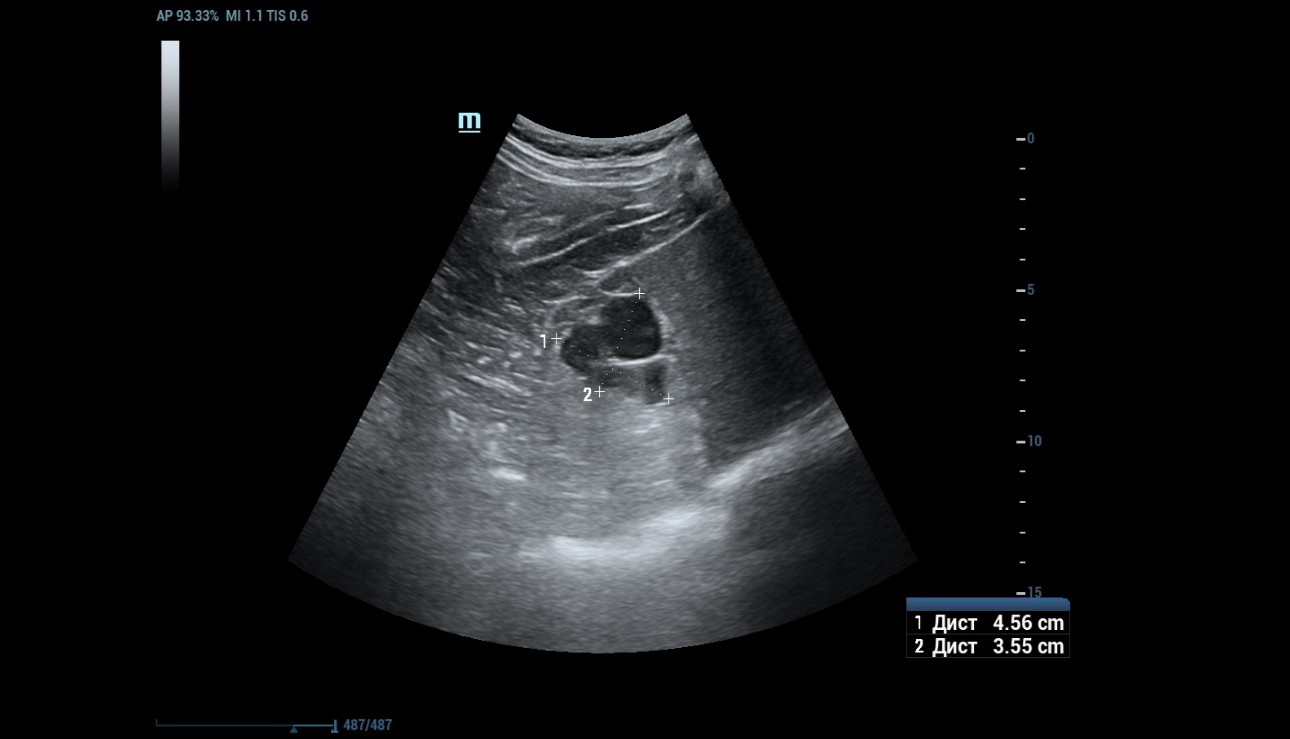

1) B-mode and Power Doppler mode imaging

An ultrasound examination was conducted using a Resona 7 ultrasound machine (Mindray, China) with the SC5-1U transducer. A cystic lesion measuring 46x35 mm in the middle part of the right kidney was found with multiple septa measuring up to 2 mm thick. When scanning the right kidney, a cystic mass with clear, even contours, 46 x 35 mm in size with multiple thick partitions (about 4 partitions) is visualized in the middle part of the cortex. It is homogeneous and anechoic within the cystic mass. A hyperechoic node measuring 10 mm in length was seen protruding into one of the cystic partition (Figure 1 and 2).